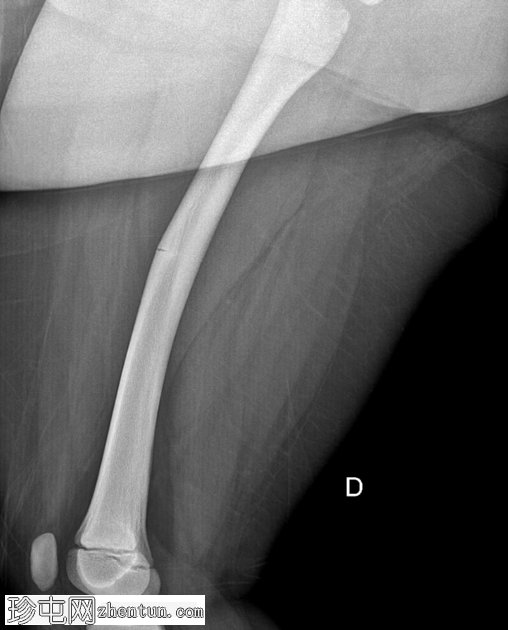

右大腿隐痛持续数日。已知有致密性骨发育不良病史。

年龄:10岁

性别:男

X光片

正面

侧面

弥漫性骨密度增高。

长骨髓质变窄。

右股骨不完全性骨折,骨折后功能不全。

双侧胫骨骨干先前骨折后出现骨重塑。